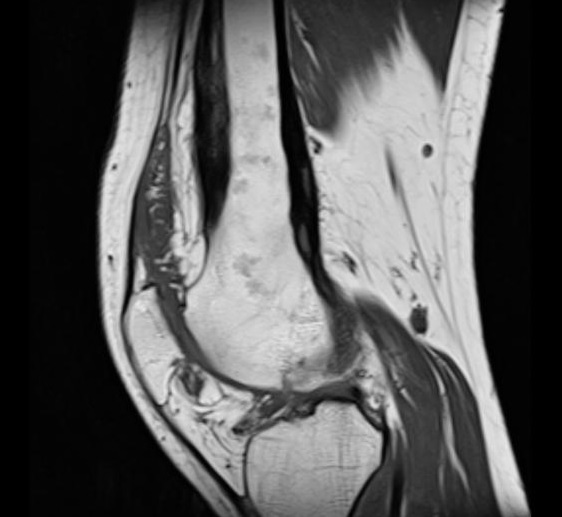

Aspect radiologique IRM de

même cas en coupe axial ponderee sur T2 . Zone

oedemateuse du lesion est hypersignal ( hyperintense

) en vue tres nette sur ce coupe . |

Aspect oedeme de la moelle osseuse

sous-chondral gauche et elargissement de

articulation steno-costale gauche .

Hypovascularisation de zone oedemateuse . |